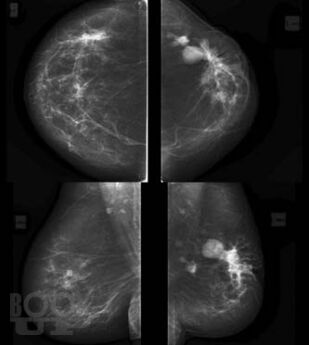

В основу книги положены материалы собственных исследований авторов и практический опыт использования комплекса новейших методик ультразвукового исследования в диагностике рака молочной железы, изучении состояния регионарных зон лимфоотока. Цель книги – помочь практикующим специалистам ультразвуковой, лучевой диагностики, маммологам, гинекологам, врачам общей практики систематизировать знания по эффективному использованию в своей практике новейших технологий ультразвукового исследования, обучить основам комплексной первичной и дифференциальной диагностики патологии молочных желез. Издание хорошо иллюстрировано, содержит большое количество рисунков, эхограмм.